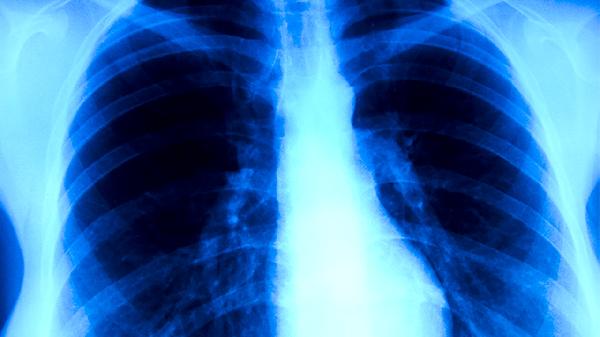

肺結(jié)核的癥狀主要有咳嗽、咳痰、咯血、胸痛、發(fā)熱等。肺結(jié)核是由結(jié)核分枝桿菌感染引起的慢性傳染病,主要通過(guò)呼吸道傳播,患者可能出現(xiàn)體重下降、夜間盜汗、乏力等全身癥狀。